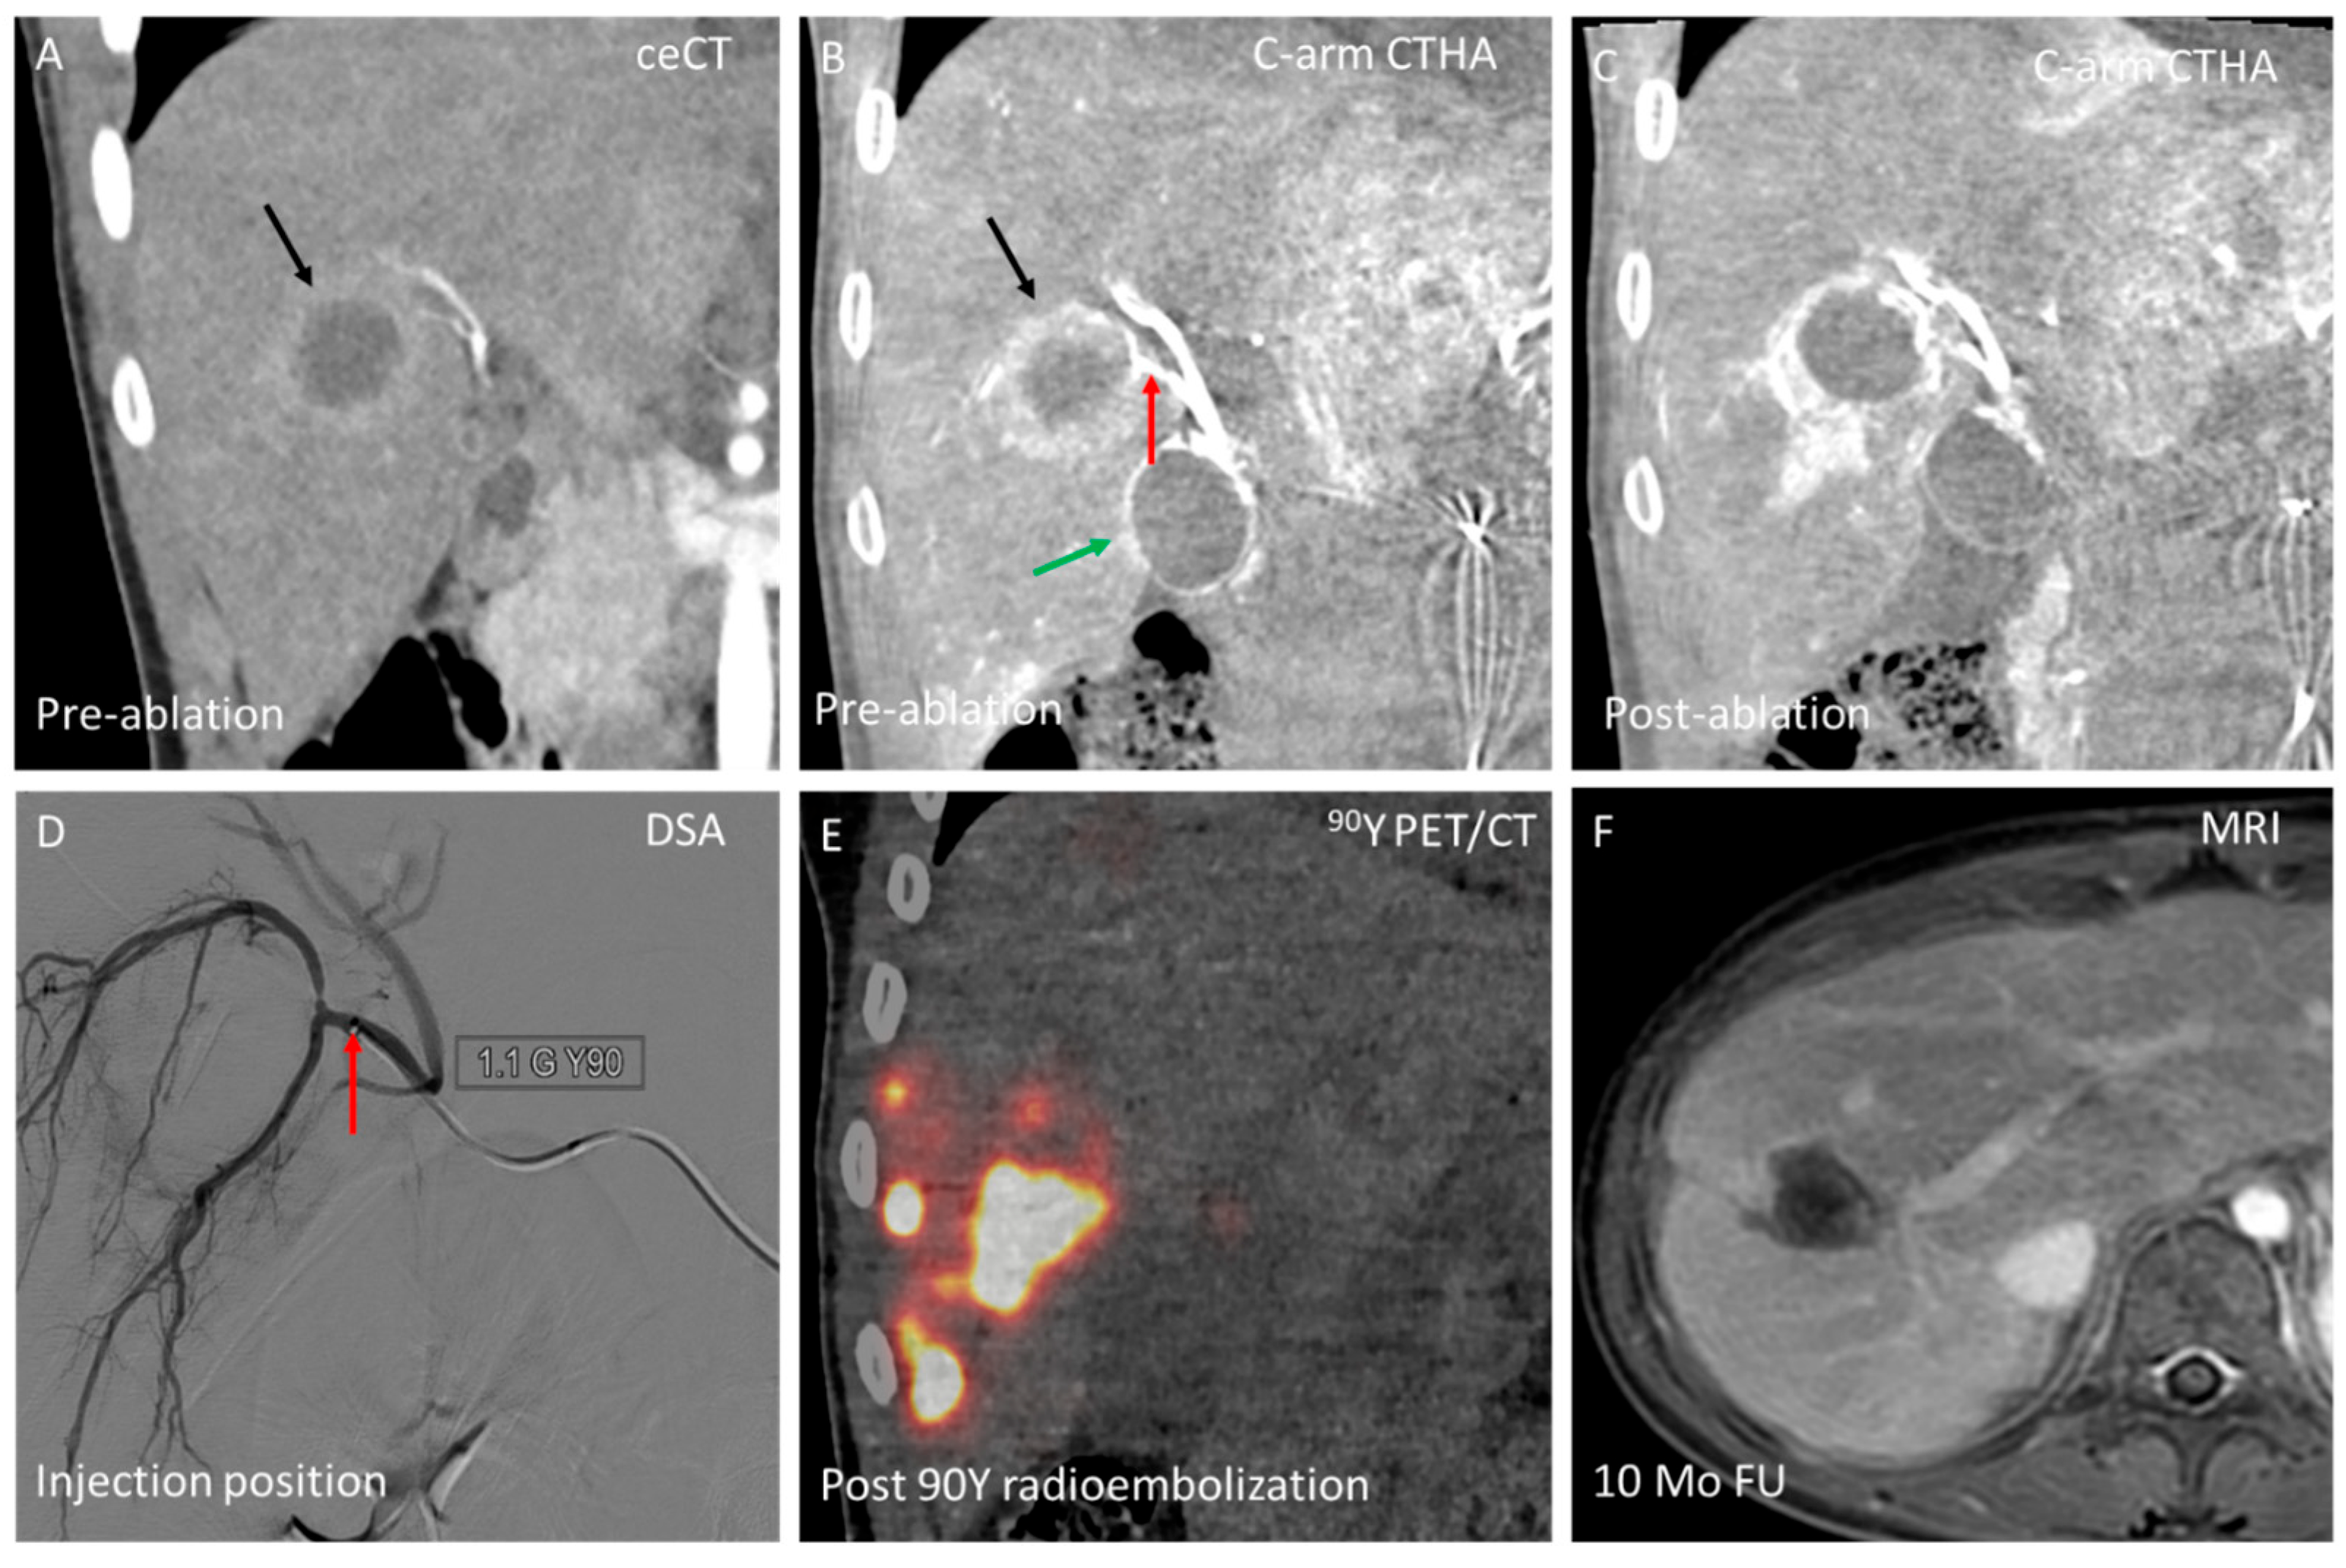

3.2. Domain B—Single-Session Combination of Ablation with Endovascular Treatment